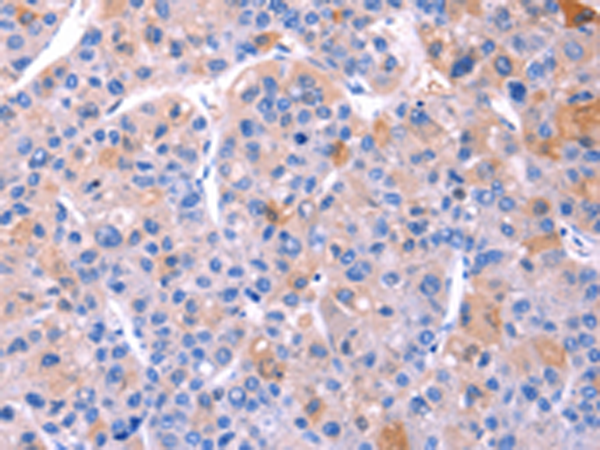

分类: 科研抗体货号: P10624别名: OOMA1; PLEIAD; C5orf25应用: IHC反应种属: Human